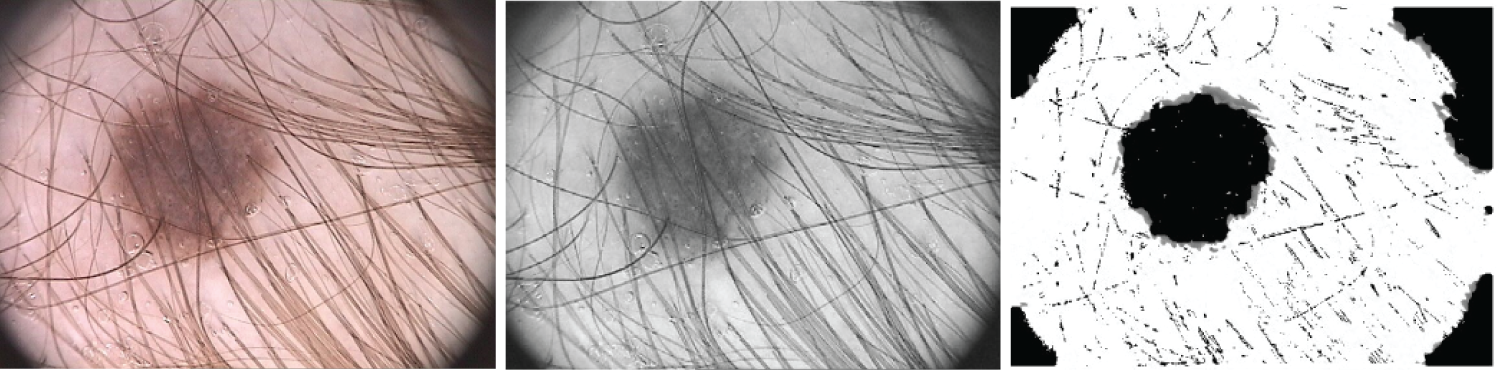

This step involves transforming the RGB images to grayscale, and noise filtering by using the dullrazor software. It is utilized since some of the acquired images are noisy because of the presence of hair and bubbles around the lesion. So Dullrazor is administered to reduce the consequence of hair being obscured on the skin in the final picture utilized for categorization, making the segmentation more accurate. Fig. 15 illustrates the output image from the pre-processing phase.

Figure 15: The original picture, the gray picture prior to hair identification and elimination, and the gray image following hair detection, exclusion, and reconstruction are the three samples for hair detection, exclusion, and reconstruction that are illustrated